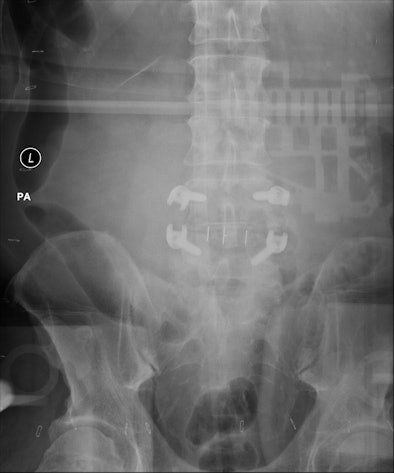

![]() |

| Backscatter artifact expressed itself as an outline of DR system electronics imposed on high-exposure images of large patients or long exposures. |

Mayo physicists fitted a phantom with pads of synthetic fat to reproduce the artifact under controlled conditions.

Based on this inquiry, they discovered that a lack of lead shielding -- possibly removed from the detector to reduce its weight and make it more marketable -- produced conditions that allowed the backscatter artifact to appear.

The problem disappeared when a lead apron was draped over the detector. The vendor then responded by taping a thin sheet of lead to the back of the detector.